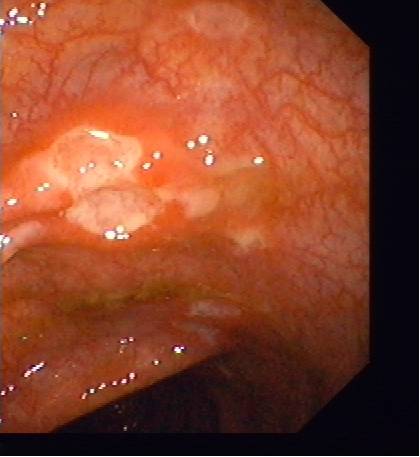

Owrzodzenie w obrębie jelita w przebiegu choroby Crohna

Owrzodzenie w obrębie jelita w przebiegu choroby Crohna